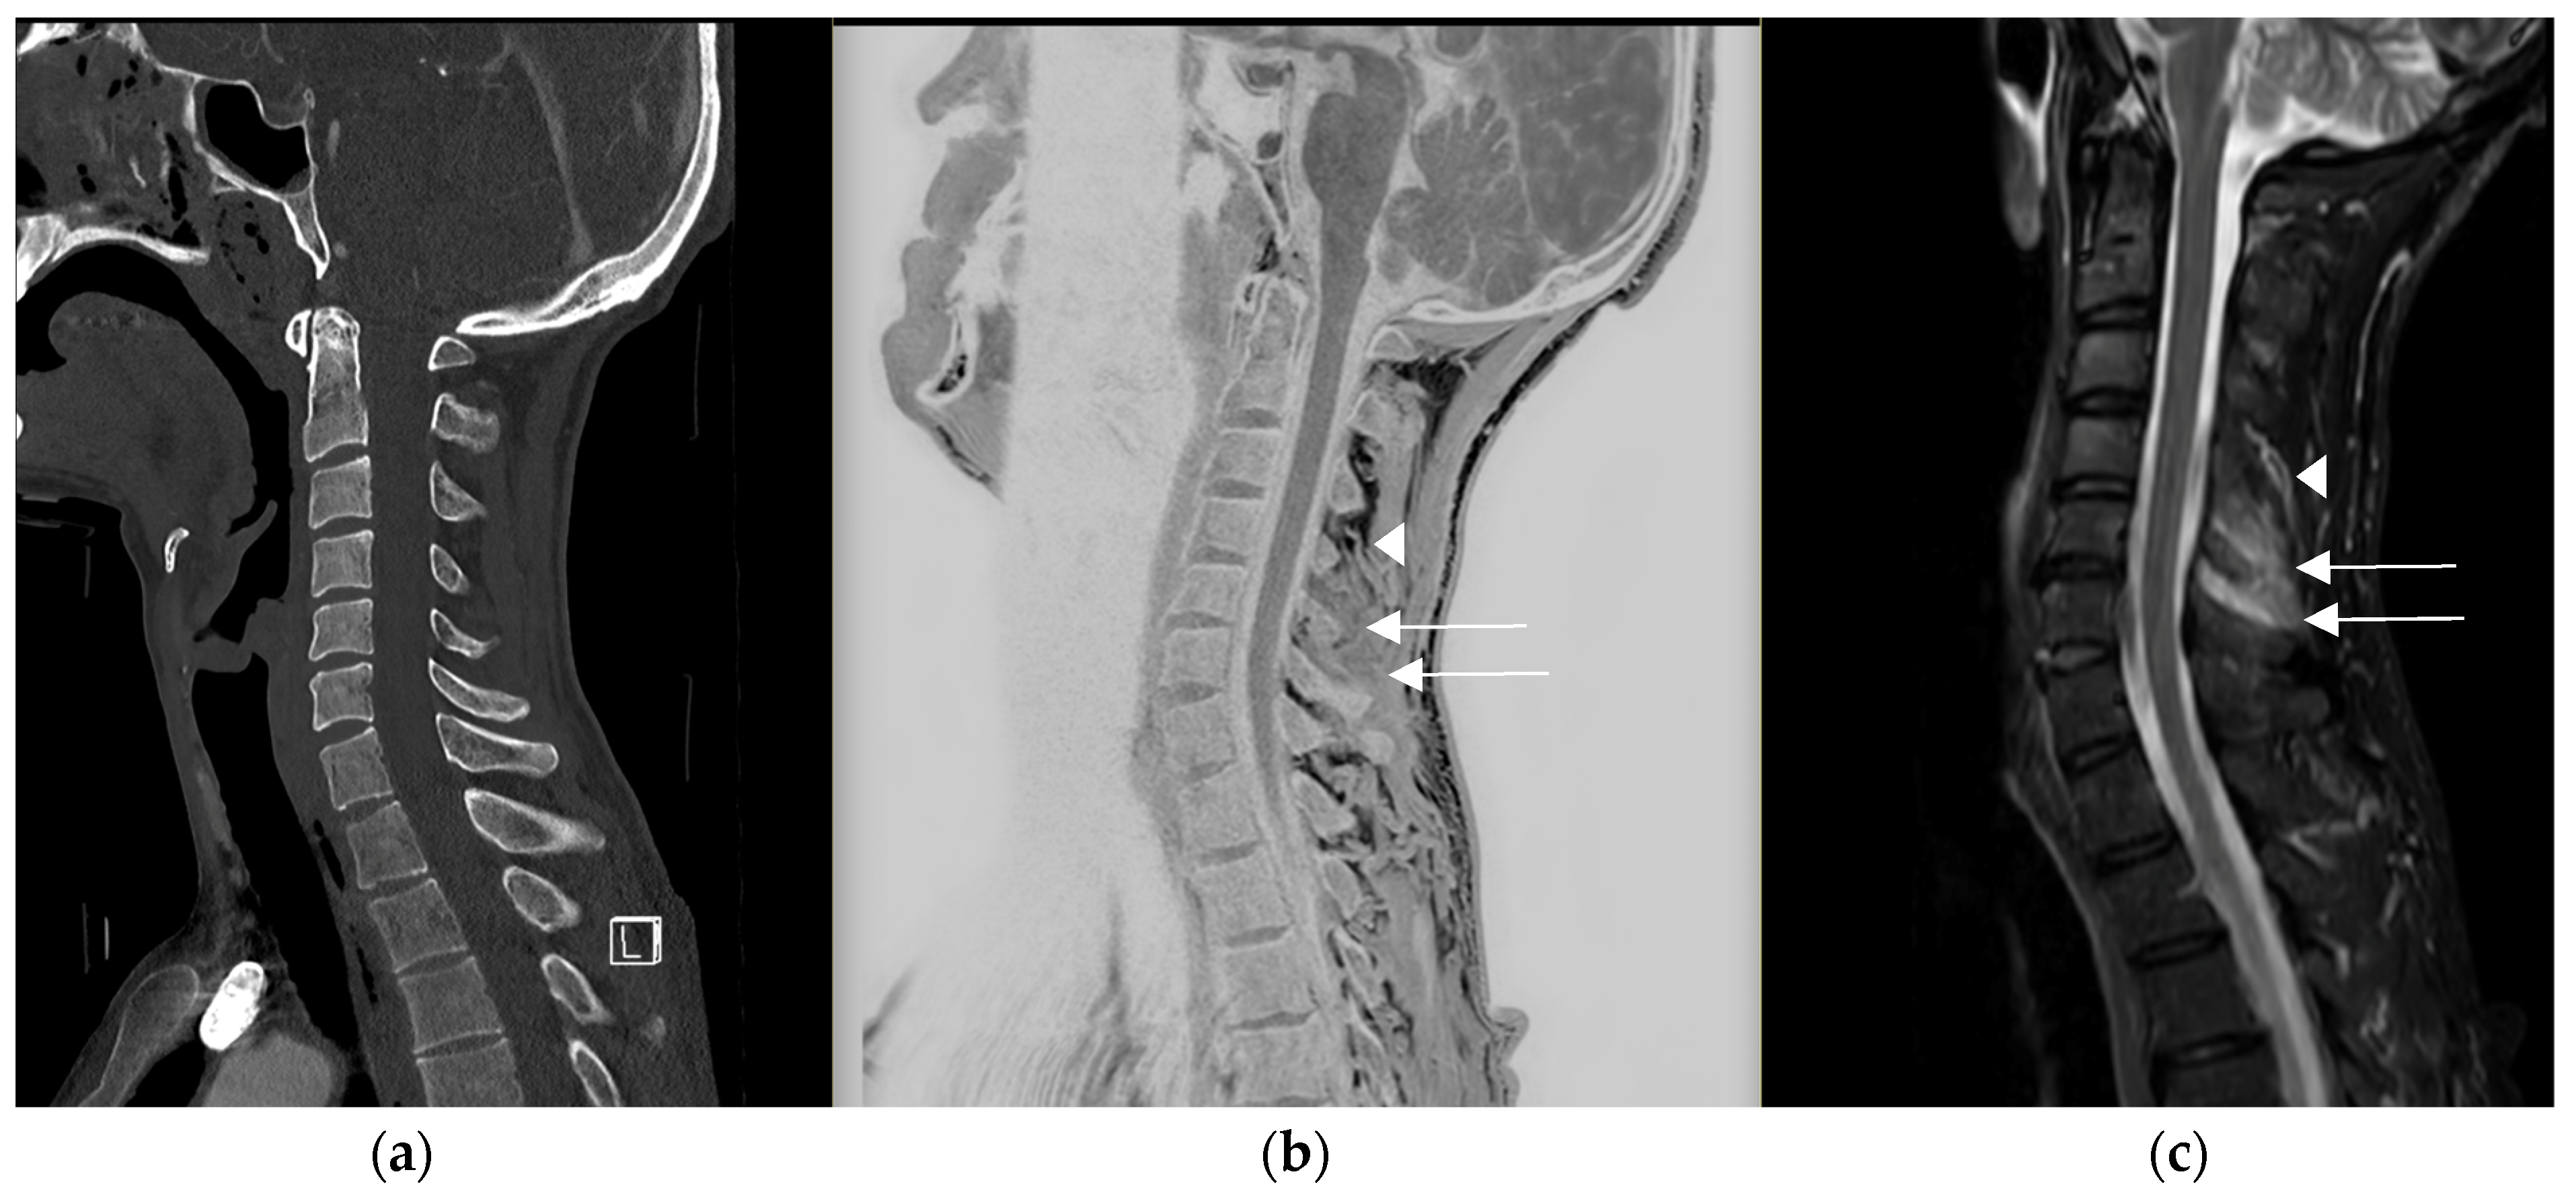

The improved contrast [14,15,16] within the soft tissues compared to CT may also be of interest in detecting the edematous infiltration [16] of these tissues, as illustrated in Figure 4.

Figure 4.

Traumatic cervical lesion in a 44-year-old patient at C6–C7, (a) initially evaluated with sagittal CT reconstruction for which, apart from the disc lesion, the analysis of the posterior ligaments was limited. (b) The CT-like sequence showed an edematous interspinous and supraspinous infiltration in C4–C5 and C5–C6 (see arrow), distinct from the vascular structures visible at the superior level in C3–C4 (arrowhead), (c) which was confirmed on the MRI protocol with the sagittal T2 STIR sequence.